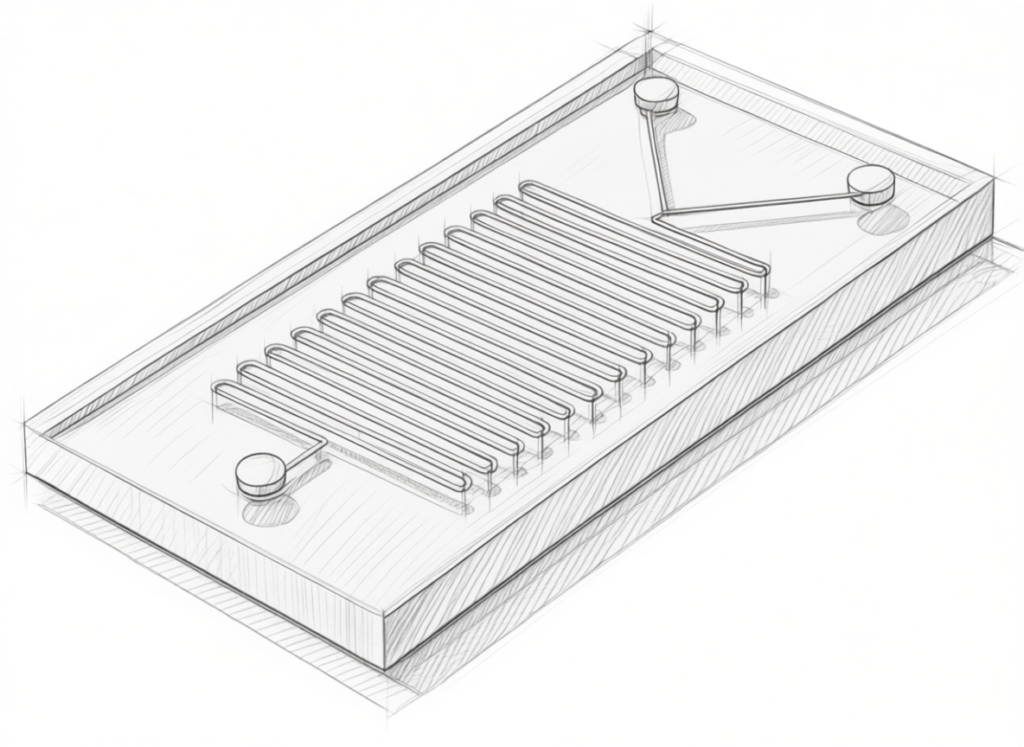

Liofilización en contínuo

iXOLAB ha desarrollado su propia tecnología de liofilización en continuo para la fabricación de comprimidos liofilizados, una forma farmacéutica innovadora que combina las ventajas de la liofilización con la administración oral sin agua. No son comprimidos en sentido tradicional (no hay compresión mecánica), sino estructuras porosas obtenidas por secado por congelación